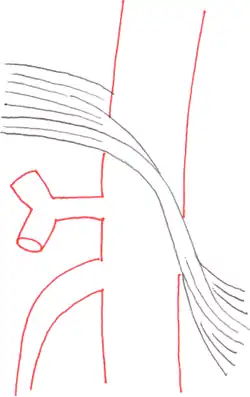

Side views (sagittal plane) of the descending aorta and two of its branches, the celiac trunk and superior mesenteric artery, demonstrate normal and MALS anatomy. Left The median arcuate ligament is normally several millimeters to centimeters superior to the origin of the celiac artery. Right In MALS, the ligament is anterior, rather than superior, to the celiac artery, resulting in compression of the vessel and a characteristic hook-shaped contour.

The median arcuate ligament is a ligament formed at the base of the diaphragm where the left and right diaphragmatic crura join near the 12th thoracic vertebra. This fibrous arch forms the anterior aspect of the aortic hiatus, through which the aorta, thoracic duct, and azygos vein pass. The median arcuate ligament usually comes into contact with the aorta above the branch point of the celiac artery. However, in up to one quarter of normal individuals, the median arcuate ligament passes in front of the celiac artery, compressing the celiac artery and nearby structures such as the celiac ganglia.[2] In some of these individuals, this compression is pathologic. It leads to the median arcuate ligament syndrome.[2]